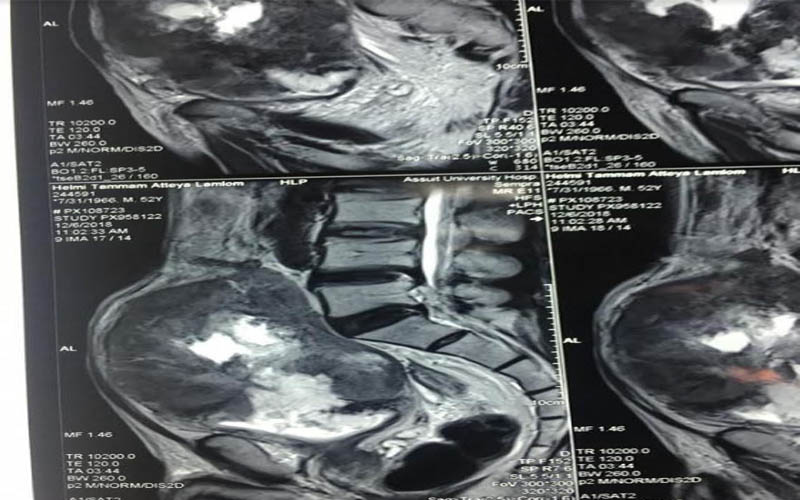

كما كشف الدكتور عمرو أبو فدان المدرس بقسم جراحة المسالك وعضو الفريق الطبي المسئول عن العملية انه فور وصول المريض إلى المستشفى تم خضوعه لعدد من الإشاعات والفحوصات الأولية والتي بينت تضخم حجم الورم مما يستلزم التدخل الجراحي لفصل الورم عن الأنسجة المحيطة وإنقاذ حياه المريض وبالفعل تم إجراء الجراحة بنجاح وخرج المريض من غرفة العمليات دون أي مضاعفات كما تم متابعة الحالة فى غرفة العناية المركزة لمدة 24 ساعة وعند استقرار حالة المريض تم نقله إلى غرفته بمستشفى جراحة المسالك البولية والكلى ، وفى السياق ذاته نوه أن نجاح العملية تم بفضل تضافر جهود الفريق الطبي بقسم جراحة المسالك البولية والكلى وعلى رأسه الدكتور حسنى البهنساوى الأستاذ المساعد بالقسم ، ومدرسين القسم وهم الدكتور أيمن عاصم ، و محمد أسامه ، وعمرو عصام ، والمعيد محمد عماد الدين ، إلى جانب فريق التخدير بقيادة الدكتور محمد أنور المدرس بقسم التخدير والعناية المركزة .

وعن تفاصيل العملية فقد أوضح الدكتور ضياء عبد الحميد الأستاذ بقسم جراحة المسالك البولية والكلى ورئيس وحدة أورام المسالك وقائد الفريق الطبي المسئول عن العملية ، أن تلك العملية تعد من أخطر عمليات استئصال أورام المثانة البولية وذلك نظراً لكبر حجم الورم واختراقه للأمعاء والأنسجة المجاورة من الشرايين والعضلات ، مما يشكل خطورة بالغة على حياه المريض والذي تم تعرضه لظروف معينة تسببت في إهماله للمرض لعدة سنوات ، مشيراً أن ذلك تم من خلال التنسيق والتعاون مع أعضاء قسم الجراحة العامة .